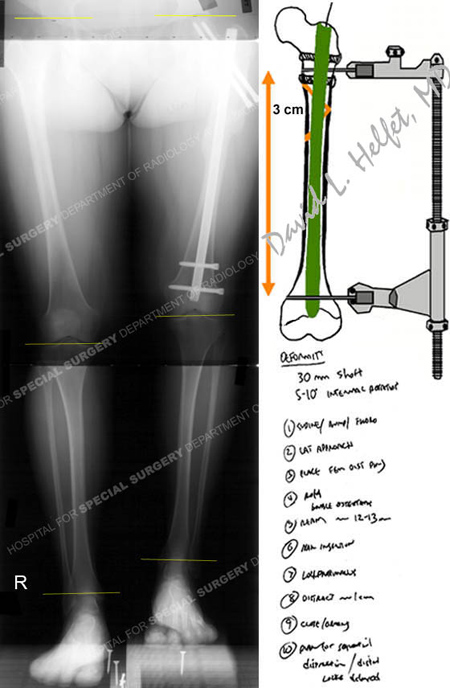

Full standing anteroposterior x-ray taken upon initial visit to HSS at 6 months following her injury revealing a left-sided healed subtrochanteric fracture with a limb length discrepancy and 3 cm of shortening on the affected side and pre-operative surgical plan for acute limb lengthening over a femoral IM nail.